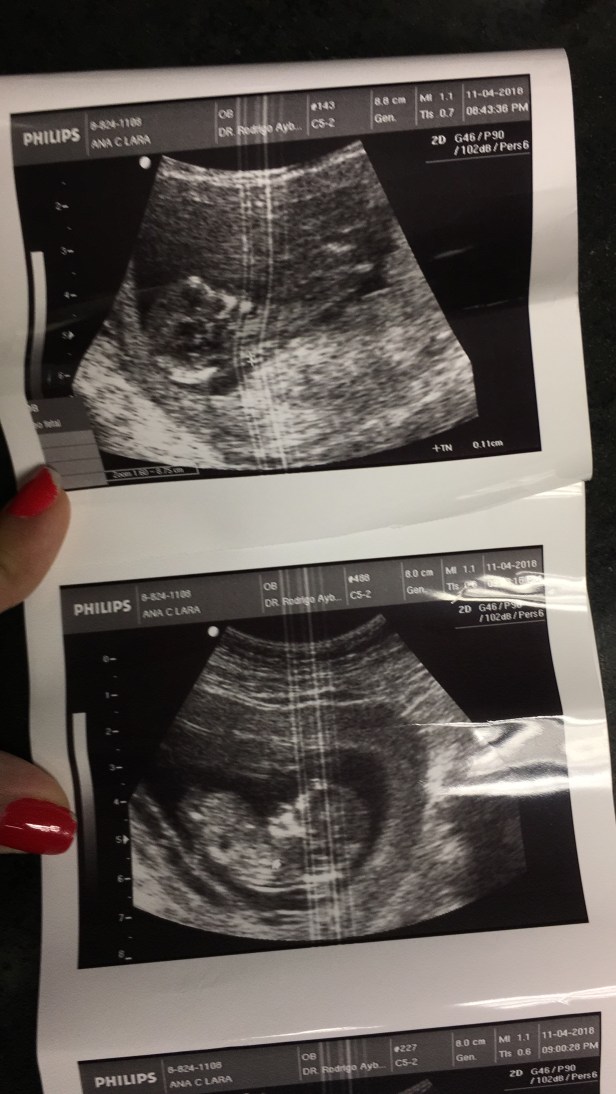

Hace unas semanas atrás me enteré que estoy embarazada, y he estado llena de muchos miedos y dudas. No solo por la posibilidad de tener otra perdida (en este post te cuento sobre nuestra perdida) sino también por todo lo que conlleva otro bebe en la familia.

Por otro lado ha sido un embarazo algo difícil pues he estado con muchos malestares, desde las nauseas a cada rato, aunque gracias a Dios ya se fueron, dolores de espalda y cadera, migrañas, falta de apetito, ganas de orinar cada 5 minutos, falta de aire, mucho sueño. La pansa también se ha crecido un montón y aveces me pregunto si el doc se equivocó y vienen dos en vez de 1 porque no entiendo como estoy tan grande con apenas 16 semanas. Mi ropa pre-embarazo no me queda por lo cual empecé a usar mis pantalones de embarazada hace como 2/3 semanas atrás.